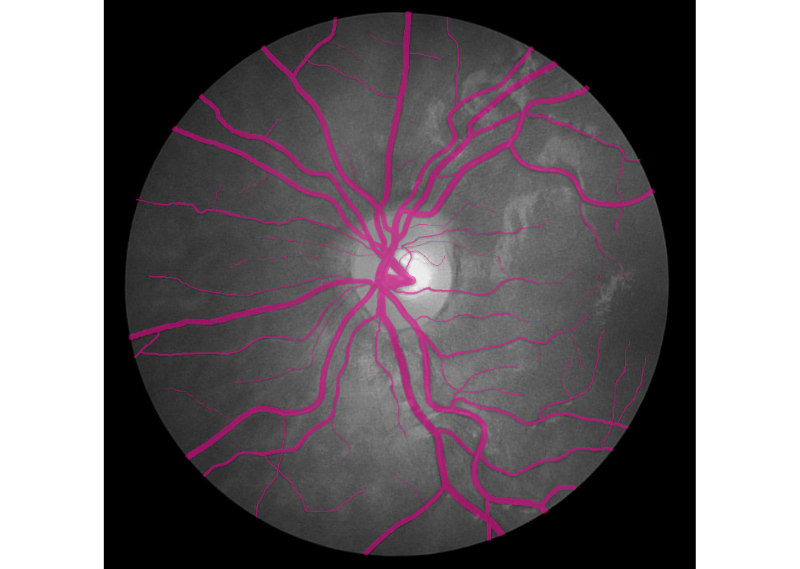

Hello world! In December of 1895, Wilhelm Röntgen the bones of his wife’s hand in the first X-ray photograph. “I have seen my death,” she said. This breakthrough had an incredible influence on 20th-century medical treatment. And latest Deep Learning advances open up new possibilities in this field. revealed Deep Learning has found great success in computer vision and other areas. And now it is actively transforming the world of medicine. AI helps doctors make more accurate diagnoses faster. Today we would like to share our thoughts and investigations into very promising direction: Human in the loop AI for medical image analysis within a single environment — . Supervisely Our platform allows to manage and annotate data, train NNs, apply them for automatic pre-annotation and then deploy them as API. Challenges with medical images IBM researchers that medical images, as the largest and fastest-growing data source in the healthcare industry, account for at least 90 percent of all medical data. estimate Challenge 1: data privacy Medical data is still personal and not easy to access. And due to data privacy concerns most of the public health centers are reluctant to share the data. Challenge 2: size of annotated data Annotation process is hard to outsource and only expert physicians can analyze medical images. This limitation leads to high costs and to the lack of annotated data. Challenge 3: quality of annotation tools Annotation tools, that can be used to extract insights from medical images, are still limited, in most cases publicly unavailable and requiring most analysis to be done manually. Challenge 4 (consequence of 1 and 2): segmentation challenge Datasets for segmentation task are typically extremely small compared to large public datasets of common images (COCO, PascalVoc and so on). Due to the size of datasets it is difficult to train very deep neural network architectures. Objects of interest can vary in size, shape and position. In combination with the “soft” boundaries it produces additional problems. Our goals We are going to overcome Challenge 3 and Challenge 4: give the industry end-to-end solution that makes human experts more efficient and automates routine tasks with powerful AI technologies. Supervisely: user interfaces We realize, that there is still a lot of work ahead: increase the number of convenient annotation tools and add the support of DICOM format, three dimensional images, sequences of images and so on. But these are only technical issues, first steps are already done and promising results are obtained. We are passioned to accelerate medicine and happy to be a part of global research community that drives deep learning revolution to healthcare. There could be no more important application of this new capability [deep learning] than improving patient care — Jensen Huang, NVIDIA CEO and co-founder Case-study: blood vessel segmentation in retina images There are a lot of Deep Learning medical applications in imaging: tumor detection, tracking tumor development, blood flow quantification and visualization, dental radiology and much more. Because we are not doctors, we looked for data we understand more or less. That’s why we decided to make research on blood vessel segmentation. Let’s take a look to one of the most popular public datasets in this field: (STructured Analysis of the Retina). STARE Dataset contains 28 annotated images with resolution 999 × 960. We consider the case that we have only . Other images will be used for final evaluation of quality. All training images are below: 6 annotated images in training dataset Here is the whole training dataset we use. This scenario is pretty close to real world: medical doctor annotates few images, then neural network is trained on this data and applied to other images for pre-segmentation. Then doctor just corrects the NN predictions. Such approach is called Human in the loop AI. It is aimed to significantly accelerate efficiency of human expert. PS. Thanks to Supervisely entire research took 2 hours without haste ☕. Step1: training data augmentation We had only 6 annotated images. To train NN we have to automatically increase the size of dataset. Supervisely has special module to perform augmentations: DTL (Data Transformation Language). It allows to configure entire augmentation process in a simple json-based format and perform it in a few clicks. How DTL query interface looks like In this use case we did horizontal/vertical flips and relatively big random crops. We got 264 training examples from only 6 annotated images. Here is the visualization of computational graph that we applied to our data: Resulted crops after augmentation Step2: train neural network There are few state of the art Neural Networks for semantic segmentation in Supervisely. One of them — our custom UNet-like architecture. It was chosen because: we have small training dataset, it is accurate and fast to train. Also we use combination of Binary Cross Entropy and Dice losses because of class imbalance problem. Vessels pixels covers only few percents of image area in contrast to background pixels. We trained NN 50 epochs. It is interesting to visualize Neural Network predictions during training. We take unseen image and apply NN after each epoch. Here you can see how our NN becomes smarter over time. Supervisely supports multi GPU training. Each epoch takes around 20 seconds on four GPU. Total training time — around 17 minutes. Step3: automatic pre-segmentation We applied NN to new images. Let’s compare predictions with ground truth. : NN predictions, : ground truth Left Right As you can see from this comparison every relatively bold vessels are segmented. There is no noise. It means that the human only have to draw few hairlines with “polyline” tool. Also, as we understand real data has much bigger resolution that public data we use in this experiment. We think that this fact is crucial for the quality of hairlines segmentation. Resolution of publicly available images is not enough. Look at this example: do you see the vessels that are annotated by doctors? Left: meme, Middle: original image, Right: doctor’s annotation Step4: manual correction As you can see from images above the quality of automatic pre-annotation is pretty good. It is much more easier and faster to correct NN predictions than annotate from scratch manually. We were not lazy and made time measurements: how much time we need for manual annotation from scratch vs correction of NN predictions. Manual annotation from scratch: . Correction of NN predictions: . 36 minutes / image 4 minutes / image Conclusion is obvious. Final thoughts Deep Learning has a huge potential in medical image analysis. AI is changing the way doctors diagnose illnesses. Main important difference between doctor and deep learning algorithm is that doctor has to sleep. Neural Network can process millions of images and can be continuously improved. Human in the loop approach and automatic segmentation with Supervisely will let us create large datasets faster. All steps are done without coding. It means that user with no ML background have access to state of the art AI. So ML community will build more services to help doctors provide better and quicker treatment. Let’s make the future together. If you found this article interesting, then let’s help others too. More people will see it if you give it some 👏.